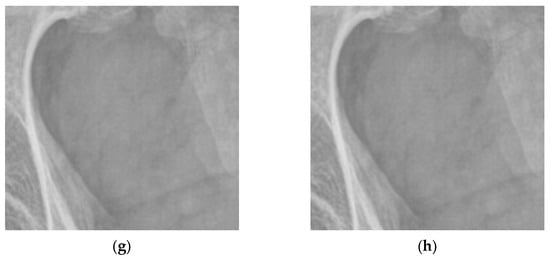

4.2. Simulations for Multiscale Noise Reduction in DR Images